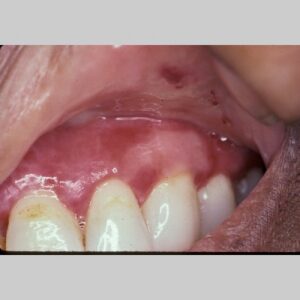

The mouth is the most frequent site of involvement in patients with cicatricial pemphigoid; it is often the first (and only) site affected. Lesions often involve the gingiva, buccal mucosa, and palate ; other sites such as the alveolar ridge, tongue, and lips are also susceptible. A frequent oral manifestation is desquamative gingivitis. Other lesions may present as tense blisters that rupture easily or as mucosal erosions that form as a consequence of epithelial fragility. Lesions in the mouth may result in a delicate white pattern of reticulated scarring. In severe disease, adhesions may develop between the buccal mucosa and the alveolar process, around the uvula and tonsillar fossae, and between the tongue and the floor of the mouth. Gingival involvement can result in tissue loss and dental complications (e.g., caries, periodontal ligament damage, and loss of bone mass and teeth).